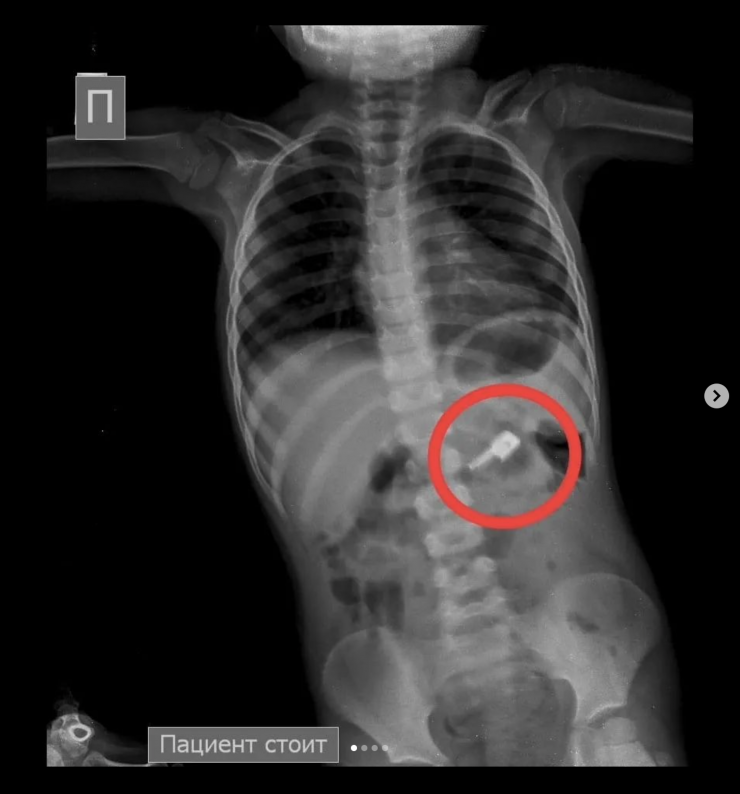

"Позже на контрольной R–грамме брюшной полости обнаружены еще две иглы в верхнем этапе брюшной полости и одна игла в проекции таза. Проведена повторная ЭФГДС, и удалена игла из желудка. Затем при помощи колоноскопии удалена игла, зафиксированная в сигмовидной кишке", - сообщил врач-хирург высшей категории Сейдахмет Чинибеков.

Однако после этого в ходе наблюдения ребенка на контрольной R–грамме брюшной полости обнаружена еще и четвертая игла в проекции таза.

"Проведена колоноскопия, и из сигмовидной кишки удалена последняя игла, которая концом была зафиксирована в слизистую кишечника. В настоящее время ребенок в удовлетворительном состоянии выписан домой", - сообщили врачи.